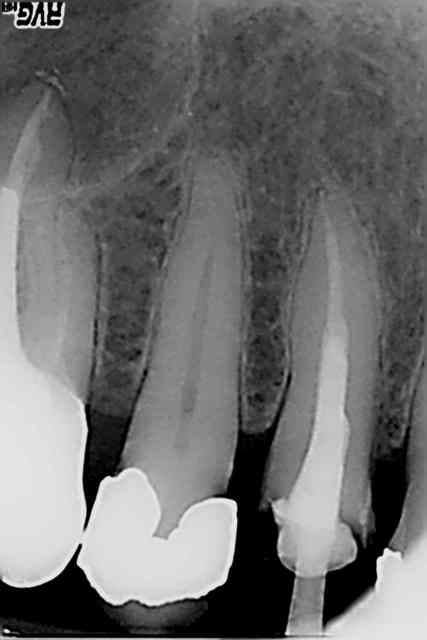

Bon je n'avais pas mis la digue sur cette 14 en 2009. A votre avis la peche en 2014 est elle due à ca ? Moralité toujours mettre de l'angulation dans les radios.